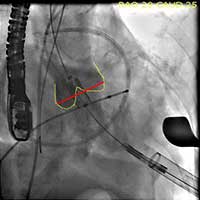

- The Sapien valve is then delivered through the introducer sheath and positioned across the aortic annulus with 50% of the valve above the annulus and 50% below the annulus. Both TEE and aortic root injection are used to confirm the position of the valve and its spatial orientation. Ideally, the valve should be in line with the long axis of the ascending aorta and perpendicular to the aortic annulus (Figure 3, 4, 5).

- The valve is deployed in position during direct fluoroscopic visualization (Figure 6) with another brief period of rapid ventricular pacing to reduce ejection. Respirations are also suspended during this period to limit the movement within the thoracic cavity and optimize visualization. Clear communication is critical during this brief period of the procedure and so one person commands the timing of each step of the procedure in a standard clear format.

Figure 6. The valve is deployed in position during direct fluoroscopic visualization with a brief period of rapid ventricular pacing to reduce ejection.

- After deployment, both TEE and another angiographic root injection are performed to confirm the position of the valve (Figure 7, 8), rule out paravalvular or central leak and to confirm the patency of the coronary arteries. Occasionally, the valve may require an additional insufflation with additional saline.